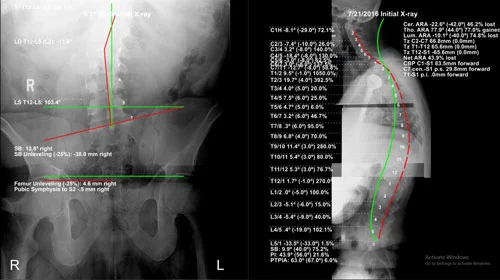

PostureRay Physics Analysis

Once the doctor has the x-rays they will do a physics analysis of each x-ray (examples to the right). Once the analysis is complete it produces a bunch of measurements for the doctor to study including angles, shifts or translations, global curvatures, and percentages from normal. The pictures are then displayed with red lines showing where your spine is and green lines showing where a normal ideal spine should be.

The doctor will go over these lines and measurements with you. That way you know and understand everything that the doctor sees and contributes to your condition. At this time the doctor will also go over the treatment plan and what they expect it to cost.

BEFORE AND AFTER X-RAYS

Once your care is complete the doctor will retake the x-rays that were previously taken at the beginning of your care. Of course these x-rays will then be analysed with the PostureRay software to give you an accurate comparison to what your spine looked like at the beginning of care.

Before

After